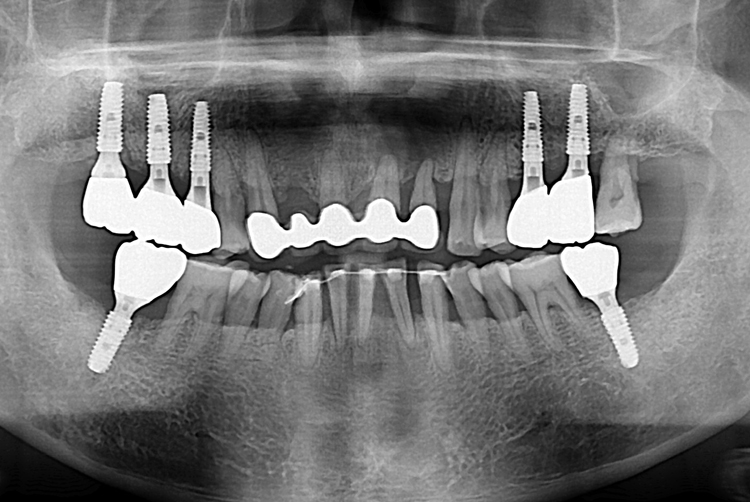

[임플란트] 어금니 임플란트

치료전 : 2019-10-22

치료후 : 2020-01-29

세종치과는 많은 환자와 다양한 케이스를 바탕으로

항상 편안한 임플란트 수술을 제공하고자 노력하고,

오래동안 튼튼히 쓸 수 있는 임플란트 수술을 가장 큰 목표로 삼고 있습니다.